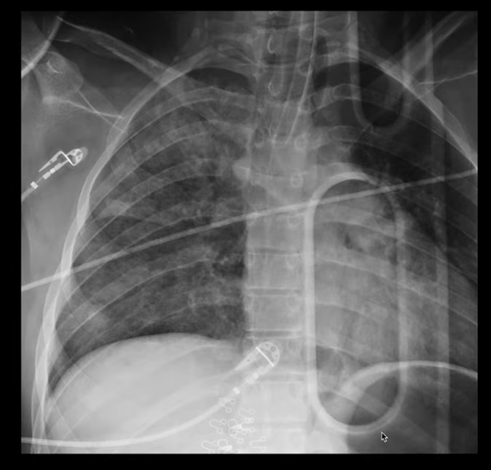

This serious complication might occur during a tracheostomy procedure if the surgeon pierces the apex of the lung.

What is a pneumothorax?